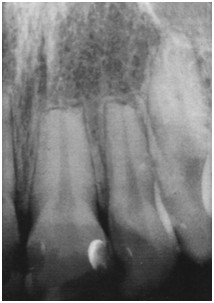

Które z przedstawionych rozpoznań jest najbardziej prawdopodobne w odniesieniu do siekaczy widocznych na poniższym zdjęciu rtg?

Pytanie 33